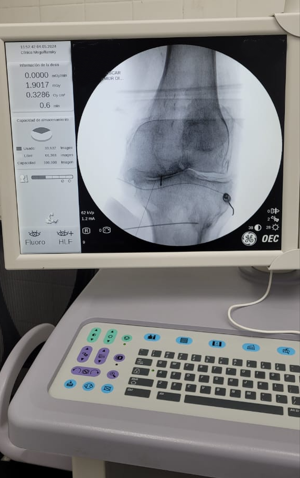

Paciente con dolor intenso por artrosis severa de rodilla

Candidato a un reemplazo total de rodilla, el paciente sentía un dolor tan intenso que le impedía la marcha.

Por la morbimortalidad de la cirugía, se procede a realizar en Tidol un tratamiento con radiofrecuencia, debido al dolor intenso que le impedía la marcha.